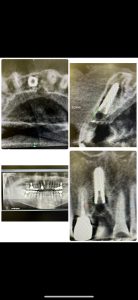

歯性上顎洞炎、順調に回復傾向

90歳メタルプレート装着3ヶ月チェックグッド👍

リムーブに、埋入、移植ボリュームアップに根面被覆👍